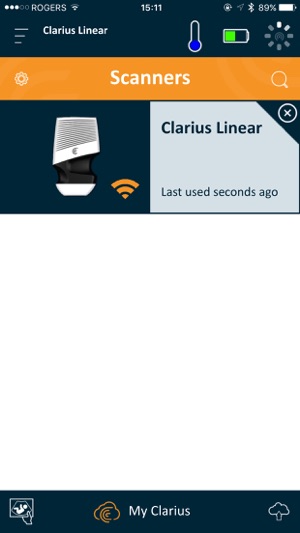

The Clarius Ultrasound App is used by trained medical professionals to operate Clarius Wireless Handheld Ultrasound Scanners. Download the Clarius App to any compatible iOS device(s) and follow the instructions to create a Clarius Cloud account and connect to your Clarius Wireless Scanner(s).